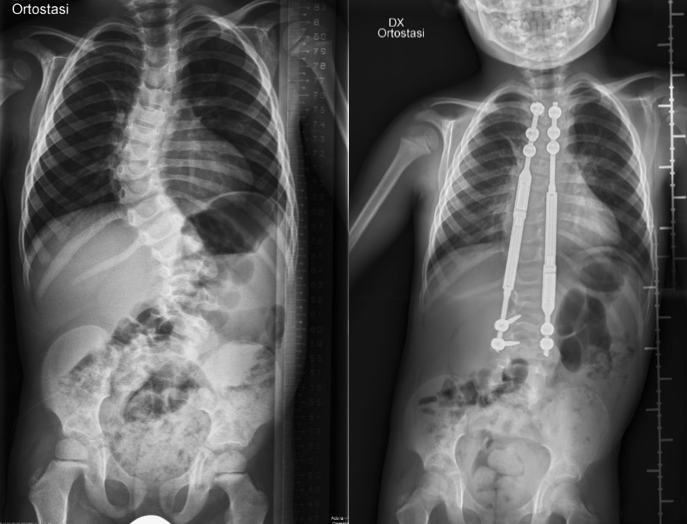

Giada è una ragazza di 16 anni affetta dalla sindrome di DiGeorge. Di questa condizione esprime alcuni tratti caratteristici, in particolare una tetralogia di Fallot diagnosticata con un’ecografia prenatale, e altri meno frequenti, come la scoliosi dorsale che ha iniziato a presentare quando aveva solo 3 anni. Se la tetralogia di Fallot è stata prontamente operata a 6 mesi di vita, lo stesso non si può dire della scoliosi, che è passata per anni di fisioterapia in fisioterapia, di medico in medico, senza mai trovare pace. Ha portato per ben 13 anni dei busti di vario tipo, che non hanno impedito il peggioramento della malattia, diventata via via più grave fino ad assumere i tratti di una vera e propria deformità (Figura 1). Alla scoliosi dorsale si è associata inoltre un’importate cifosi, che rendeva faticoso persino guardare negli occhi i genitori. Finalmente, a 16 anni compiuti, la ragazza è stata sottoposta a intervento chirurgico correttivo mediante il posizionamento di un sistema allungabile di uncini, in modo da intervenire sulla patologia senza pregiudicare un adeguato accrescimento della colonna vertebrale, e di una trazione halo, per la correzione simultanea della cifosi associata. Il risultato, vista la condizione di partenza, è stato comunque buono, ma non eccellente, causa la tardività dell’intervento.